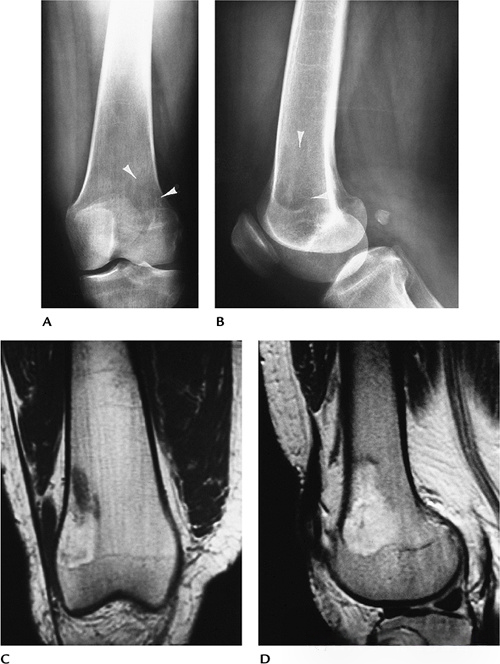

2ff728fd1efe9dbf84a9dc73c3b14e3a.png

图-10骨黄色瘤(Ⅳ型高脂蛋白血症)。(A、B)X光片显示股骨远端有一个边界不清溶骨性病变(箭头)。冠状位T1(C)和矢状位T2(D)显示一个边界不清病变,T1(C)上呈现脂肪信号,在T2(D)上呈现高信号区。